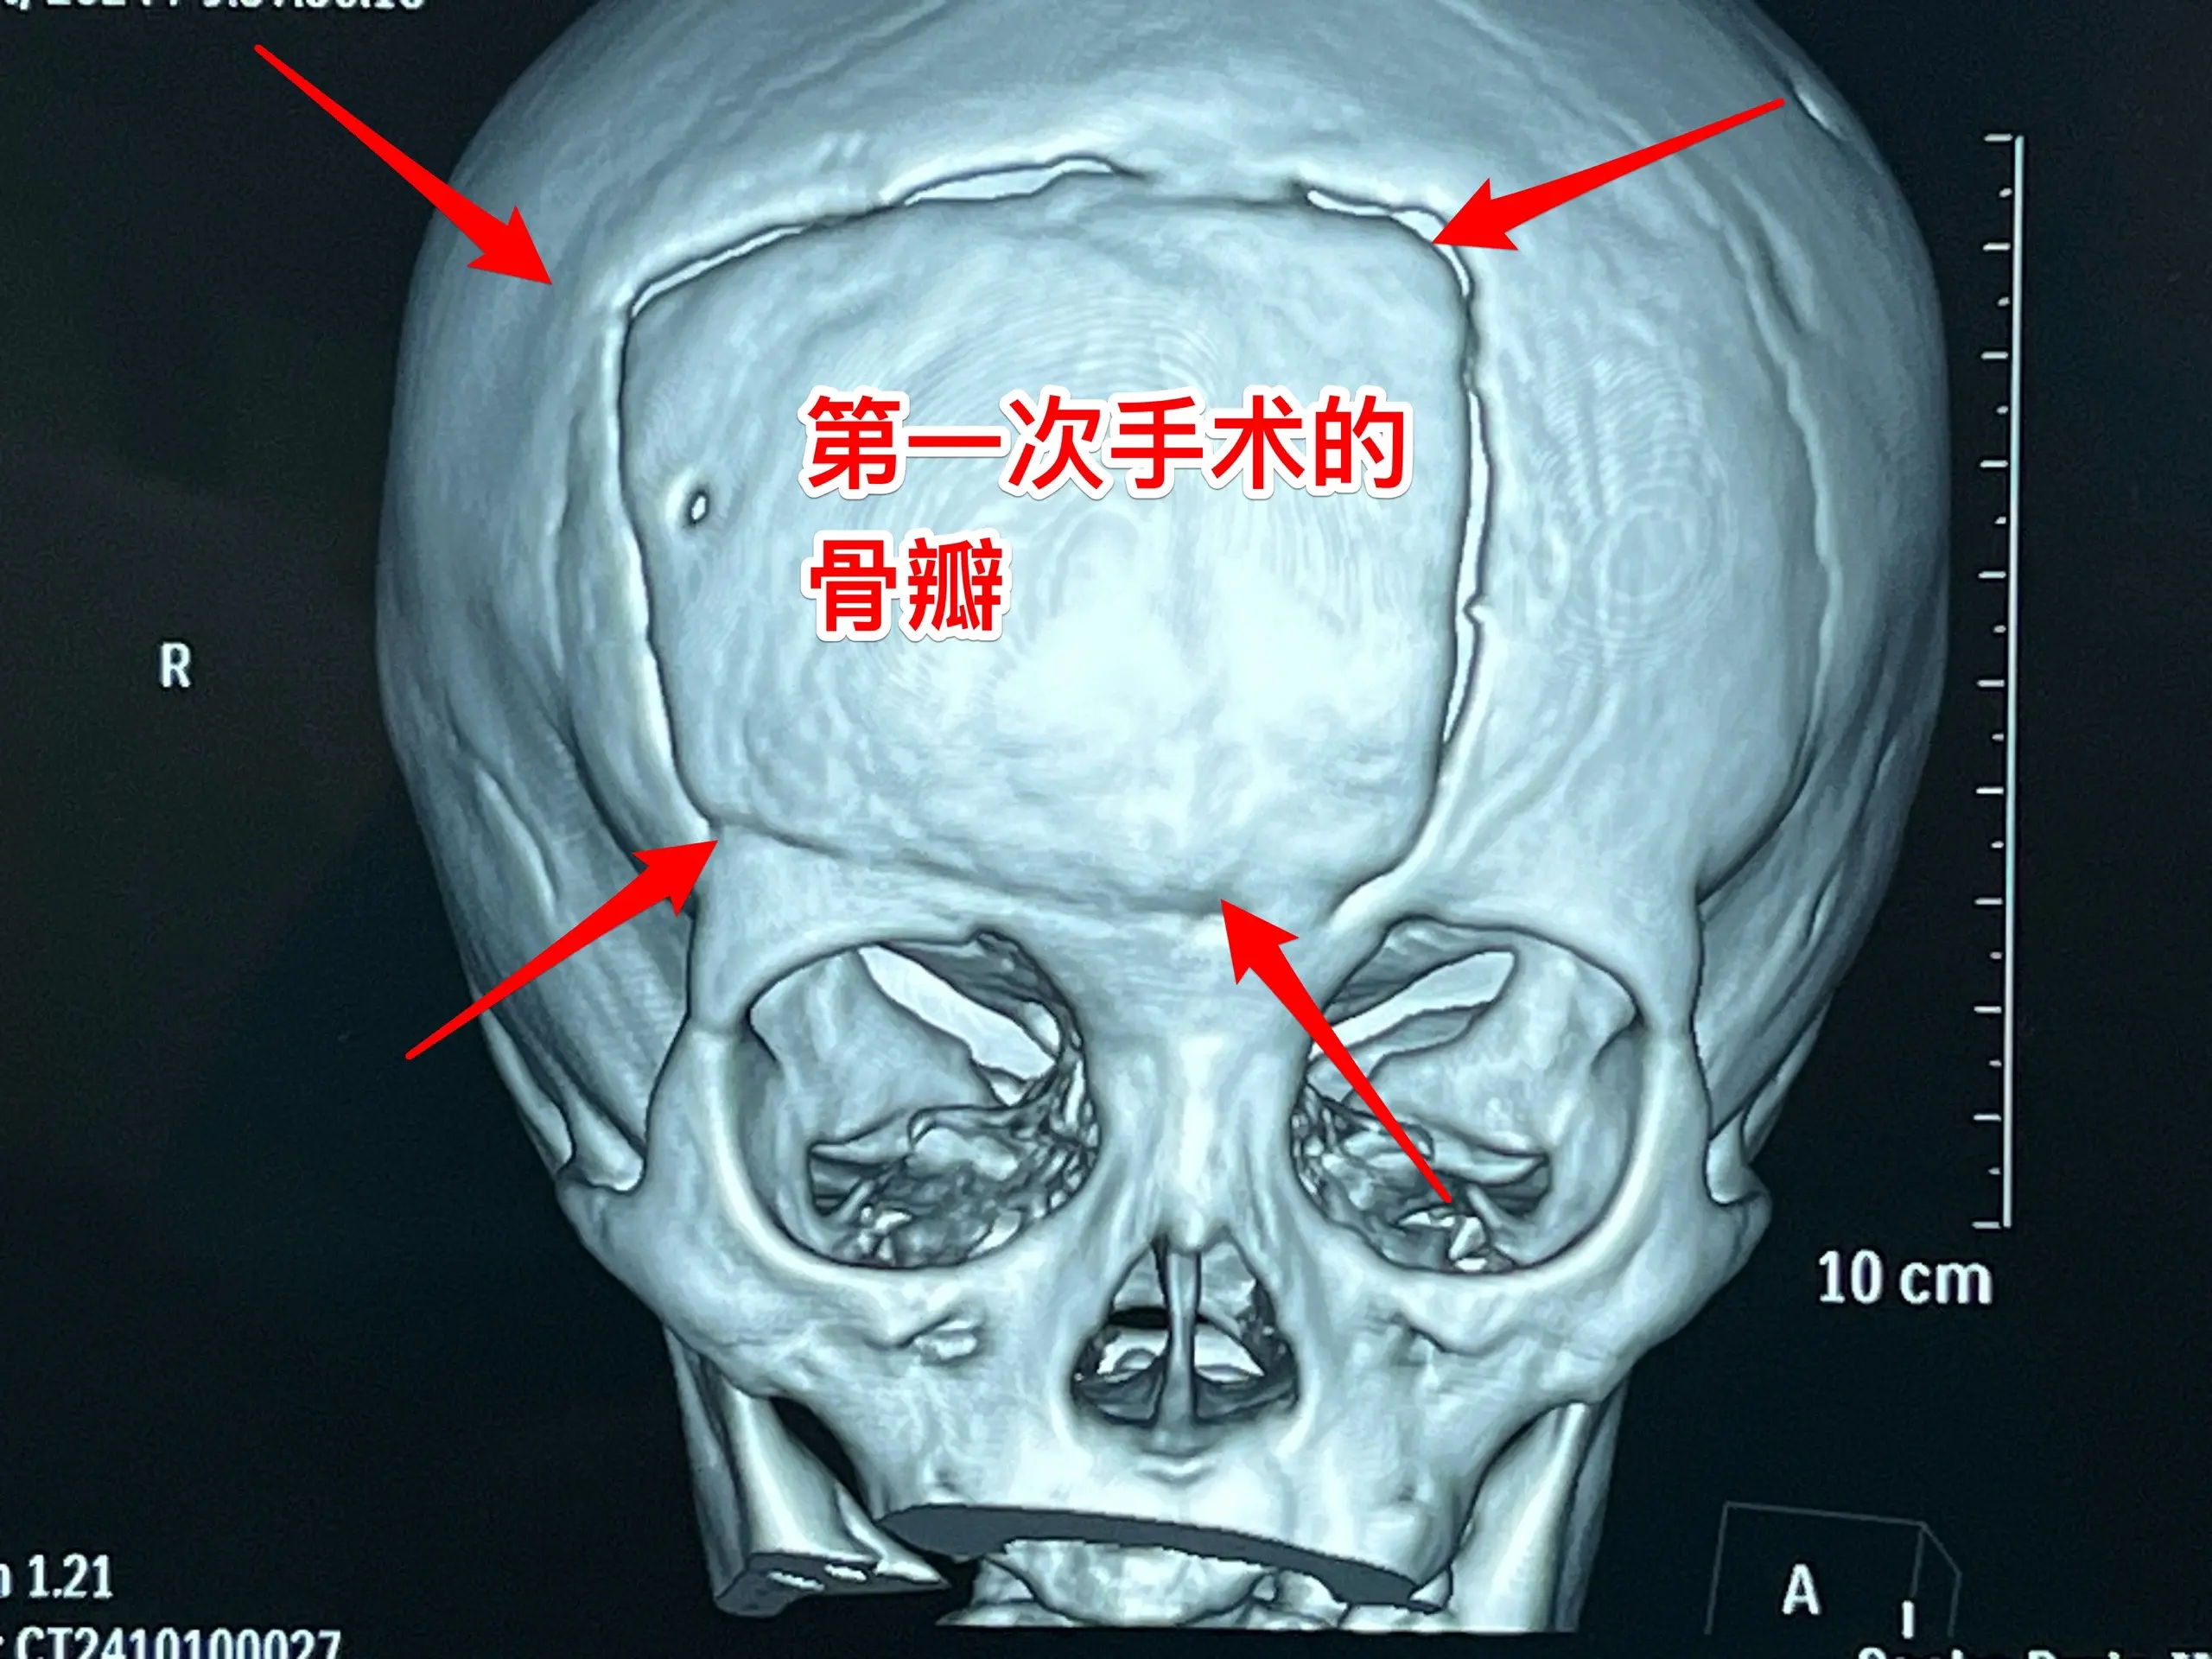

今日两个颅咽管瘤手术。1,6岁男孩子,安徽宿州人。2023年5月因视力下降发现了脑部长了巨大颅咽管瘤,见图1。家长曾经通过微信找我看过,最终选择在上海某医院行手术治疗,手术后出现右侧偏瘫,经过康复治疗后能勉强走路,但是右手还不能拿笔写字。2023.12磁共振就显示颅咽管瘤复发了(多块肿瘤复发)。2024.10又出现视力下降,故来找我作手术。今天手术中发现有四块较大的肿瘤,同时有很多个小钙化。所见肿瘤均顺利切除了。对比两次手术前的磁共振,可以说第一次手术更容易达到完全切除肿瘤,很遗憾,那一次机会错过了。 2,9岁男孩子,江苏盐城市的。因头痛、呕吐检查发现脑部有典型的颅咽管瘤,伴有脑积水。病人到我科住院后经用甘露醇和地塞米松后头痛、呕吐症状消失,能正常吃喝。今日作了开颅手术,顺利切除肿瘤。